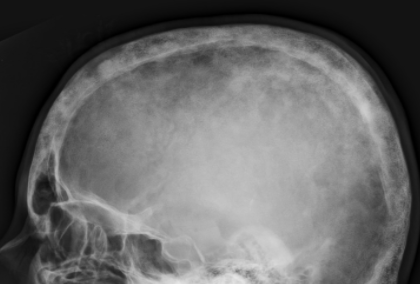

Cotton Wool Skull

- Patchs de sclérose dans un crane lytique

- Risques d’atteinte neurologique à la base du crâne

- Epaississement des corticales et trabéculaire